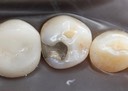

Joe Cha #19 pre-op

Joe Cha #18 pre-op